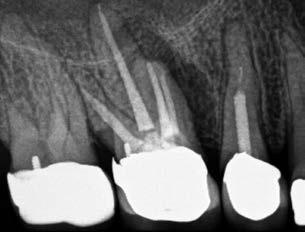

1. a-n. ábrák: Preoperatív CBCT-felvétel a bal alsó 6-os (3.6) fogról. Az axialis (a), coronalis (b) és sagittalis (c) nézeteken a mezialis és distalis gyökerek apicalis harmada körül sugáráteresztő zóna és ép buccalis corticalis csont látható. Egy olyan sablont terveztünk, amely jelezte a csontablak határait az apicalis terület pontos elérése érdekében (d). A mikrosebészeti bevatkozás során a sablont a helyére illesztettük (e), a csontablak határait megjelöltük (f) egy Piezotome CUBE LED kézi-darabba fogott fűrésszel, majd kivágtuk és eltávolítottuk (g és h) az apicalis területhez történő hozzáférés, illetve a mezialis és distalis gyökerek rezekciójának, retrográd preparációjának és retrográd gyökértömésének elvégzése érdekében (i). Végezetül a csontablakot visszaillesztettük és kollagén szivaccsal stabilizáltuk (j). A műtét után közvetlenül készített röntgenfelvétel a 3.6-os fogról (k). A kétéves kontroll során készített CBCT-felvétel: axialis (l), coronalis (m) és sagittalis (n) nézetek.

Egy 63 éves páciens korábban már kezelt bal alsó első nagyőrlőfogából (3.6) eredő mérsékelt fájdalom miatt kereste fel rendelőnket. A kórtörténetében panasza szempontjából releváns információ nem szerepelt. Az elkészült CBCT-felvételen a korábbi kezelések során észre nem vett, jelenleg feltáratlan meziobuccalis csatornát, valamint a mezialis és distalis gyökerek körül kialakult periapicalis elváltozást, és ezt a léziót borító intakt buccalis corticalis csontlemezt láttunk.

Klinikai vizsgálat során vertikális kopogtatási érzékenységet jelzett. A fog körül mérhető szondázási mélység és a fogmobilitás fiziológiás volt. A CBCT-felvételen nem észleltünk a csontos regeneráció megindulására utaló jeleket (1. a–c. ábrák). A korábban gyökérkezelt, gyökértömött és revideált 3.6-os fog esetében az alábbi diagnózis került felállításra: periodontitis periapicalis symptomatica. A panaszokat okozó fog további ellátása során navigált endodonciai mikrosebészetet kívántunk alkalmazni. Az alsó állcsontról intraorális szkent (TRIOS, 3Shape) készítettünk, és a felszíni topográfiát tartalmazó STL fájlt, valamint a CBCT-felvétel készítése során nyert DICOM fájlokat a Blue Sky Bio szoftver segítségével egyesítettük. A sebészi sablon megtervezésére az így kapott háromdimenziós képet használtuk. A sablon kialakítása során arra törekedtünk, hogy a sablon egyértelműen meghatározza a gyökércsúcsi terület eléréséhez szükséges csontablak határait (1. d. ábra)